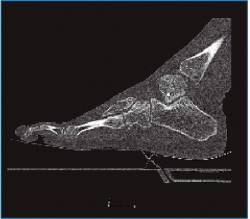

En la exploración destaca una inflamación y dolor en el borde externo del pie que no impide la deambulación. En la revisión de las pruebas complementarias (radiografía simple y TC) se confirman las lesiones previamente diagnosticadas, junto con una luxación del cuboides plantomedial (Figuras 1 y 2).

Figura 2. Imágenes de la tomografía computarizada (TC) que ponen en evidencia la fractura de la base del 4.º metatarsiano con la luxación plantar del cuboides.